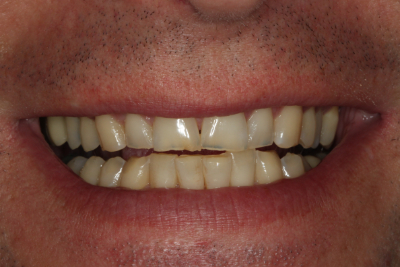

二次元評価から、咬合不安定性の徴候は明らかでした。 ダレンは、切歯縁が非常に薄く、欠け、透明になりつつあるほどでした。 上顎前歯の舌側にはほとんど棚が装着されており、機能的な包絡線が制限されていることが示唆されました。 また、前歯だけでなく後歯にも象牙質への摩耗があり、前歯はクラス1の可動性を持っていました。

審美的には、彼の上顎切歯縁はわずかに垂直方向に欠損しており長さを伸ばす必要がありました。 ダレンは咬合平面がわずかにカントしていましたが、本人はその矯正には興味がありませんでした。 下顎切歯面やアーチフォームも改善が必要でした。

私たちの目標は常に、可能な限り最高の機能的結果を達成し、患者の目標を満たすために必要な最小限の歯科治療を行うことであるべきです。 ダレンは伝統的な歯科矯正に興味がなかったので、私たちは彼の機能の包囲の自由度を増加させ、前歯部咬合関係を改善するためにクリアアライナー療法から開始することを選択しました

歯科矯正はまた、歯の準備でより保守的にすることができました。 上顎切歯の舌側には、すでにかなりの歯質が磨耗していたため、削らなければならない歯質の量を最小限にしたかったのです。 また、矯正歯科では、前方誘導のために必要な下顎前歯の前処置や間接補綴を避けることができます。